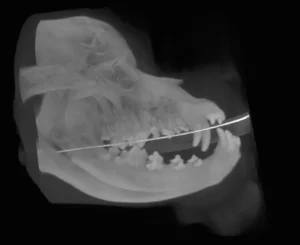

With this CT imaging system the entire head can be imaged in a single 18 second scan, allowing evaluation of teeth, jaw bones, maxillofacial anatomy, sinus and nasal cavities. CT images are composed of slices which allows millimeter by millimeter detailed assessment. In addition, a computer-generated three dimensional image may be produced. These images are superior to regular x-rays for evaluation of maxillofacial fractures, temporomandibular joint dislocations, and oral cancer.

Sample Images